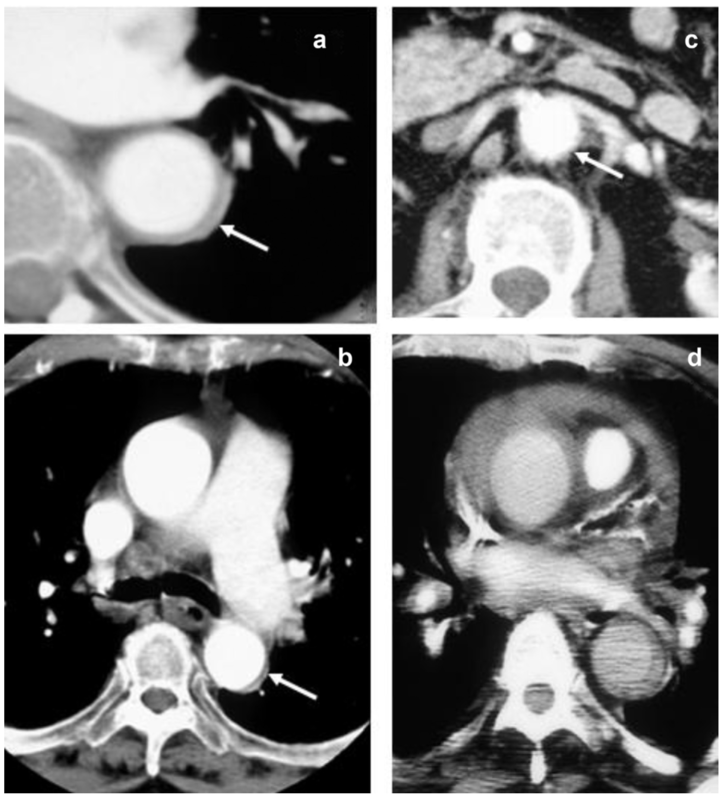

- 超音波断層走査で側頭動脈、後頭動脈または滑車上動脈に低エコーの同心性血管壁肥厚(hypoechoic halo sign)が認められる。